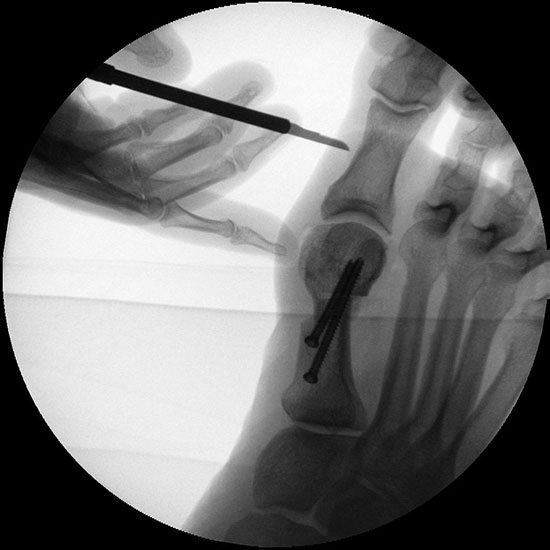

Abbildung 1

• Korrekturpotential größer als beim offenen Chevron, da die Gelenkkapsel als stabilisierendes Element erhalten bleibt und über eine trikortikale Osteosynthese mit zwei kanülierten Schrauben eine Verschiebung bis ca. 80% des Metatarsaledurchmessers möglich ist (Abb. 1).